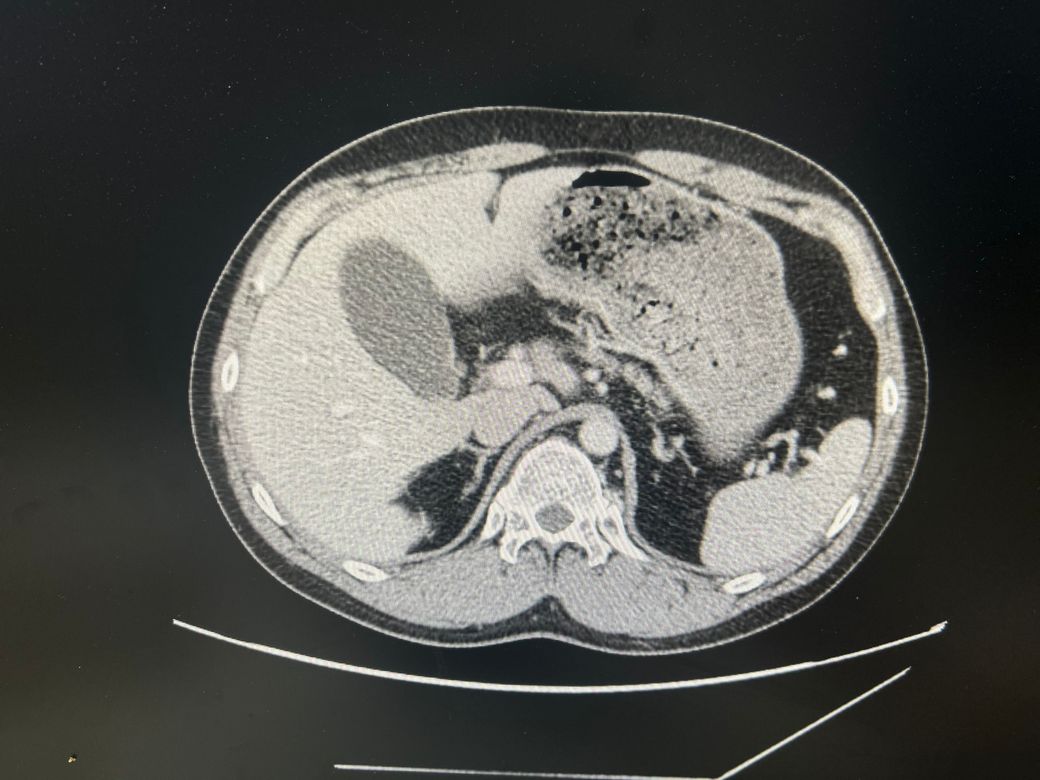

담낭염일 까요?? (CT 사진 있어요)

우상복부 통증(좌상복부 통증도 생김), 오른쪽 어깨에서 허리까지통증, 소화불량, 팽만감,답답함, 설사 증상이 있는데..... 담낭염이 맞을까요?

• 4번 째 사진

CT에서 담낭염은 담낭벽이 두꺼워보이고 벽이 조영증강되는데

환자분 자료의 경우 그런 소견이 뚜렷하게 보이지는 않는 것 같습니다.

• 애매합니다. 담낭의 크기가 다소 늘어나 보이긴 합니다만, 당남염을 강력하게 의심할만한 다른 소견들이 보이지는 않습니다. 가령 담낭의 벽이 두꺼워지거나 담낭 주변의 염증 소견, 담낭 목을 막고 있는 담석 등이 따로 관찰되거나 하지는 않기 때문에 담낭염을 강력하게 의심하기는 어려워 보입니다. 우상복부의 압통 및 머피징후 등의 신체검진 소견이 있다면 담낭염의 가능성을 고려해볼 수 있겠습니다만, 해당 CT 소견만으로는 판단하기 어렵습니다.

첨부해주신 CT 영상에는 담낭 주변에 두드러지는 염증소견이 관찰되지 않습니다. 다만 영상의 모든 단면을 확인한 것이 아니라서 담석증의 여부에 대해서는 확답드릴 수 없습니다. 증상이 지속되면 내과에서 진료를 받아보시는 것을 권해드립니다.